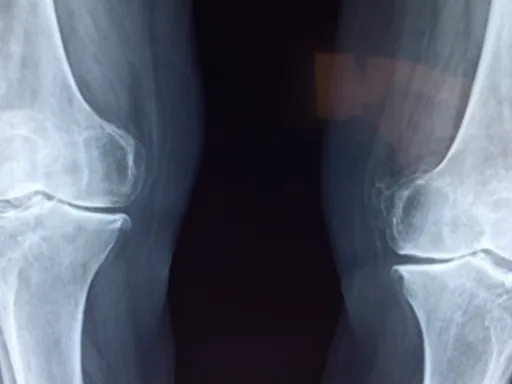

보스웰리아 는 관절 건강 개선에 있어 특히 주목받고 있는 성분입니다! 이 식물에서 추출한 유효 성분인 보스웰릭산이 관절 통증과 염증을 완화 하는 데 큰 역할을 한다고 알려져 있죠. 많은 연구에 따르면, 보스웰릭산은 특정 염증 경로를 차단하여 체내 염증 반응을 조절하는 효능이 있습니다. 실제로, 한 연구에서는 보스웰리아 추출물이 관절염 환자의 통증을 30% 이상 감소시켰다는 결과도 있답니다!

특히, 관절염으로 고통받는 분들께는 보스웰리아가 효과적인 보조 솔루션이 될 수 있습니다. 그 이유는 관절의 관절막과 주변 조직의 염증을 줄여주기 때문이죠. 지속적인 연구에서 보스웰리아가 류마티스 관절염과 같은 만성 염증 질환에도 긍정적인 영향을 미친다는 결과가 나왔어요. 실제로, 연구에 참여한 환자들 중 상당수가 보스웰리아 섭취 후 관절의 움직임이 한층 더 개선되었다고 보고했답니다!